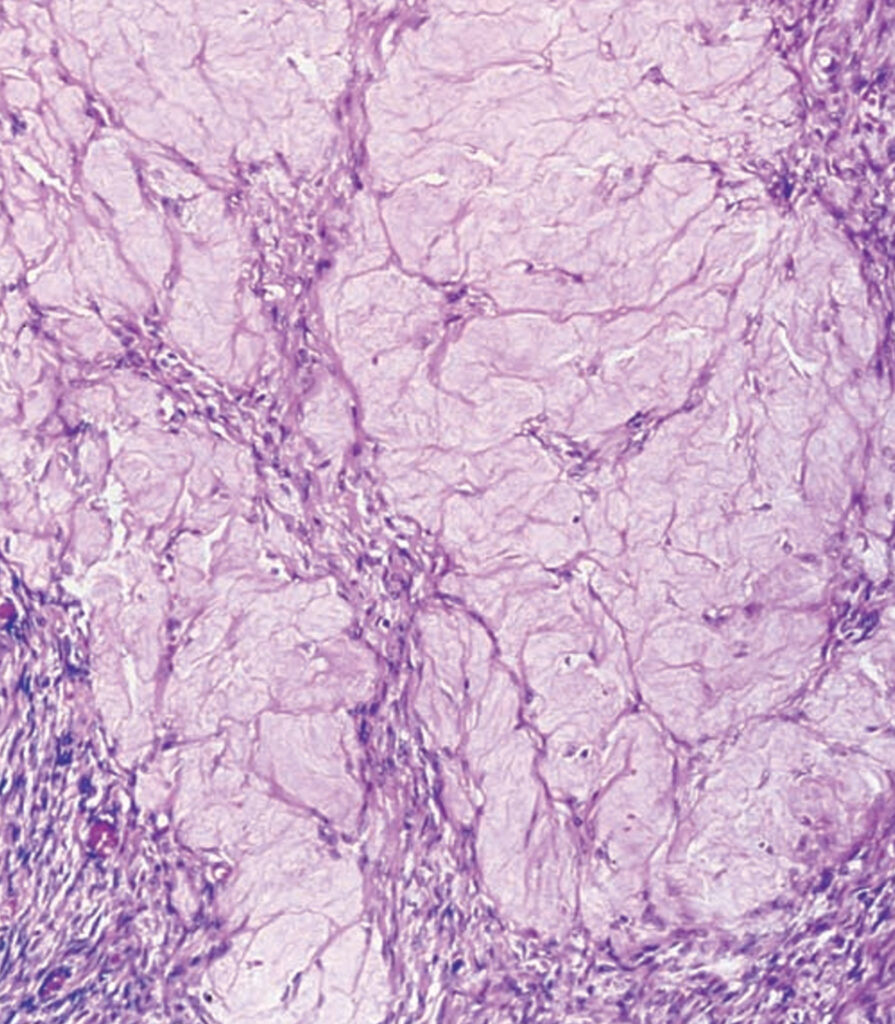

La capa cortical está constituida por tejido conjuntivo, cuyas células están muy próximas unas a otras. Existe, por tanto, escasa sustancia fundamental interpuesta entre los elementos celulares. Estas células, que constituyen el estroma, pueden producir hormonas esteroideas. Inmediatamente por debajo del epitelio germinal existe una delgada zona, en la que el estroma es más denso, que se denomina túnica albugínea.

En la zona cortical del ovario existen una serie de elementos que experimentan modificaciones cíclicas durante la vida de la mujer y que constituyen la dotación germinal. Estas formaciones reciben distintos nombres, según su estadio evolutivo: folículos primordiales, folículos en maduración, folículos de De Graaf, cuerpos lúteos, corpus albicans, folículos atrésicos y folículos fibrosos. La constitución histológica de estos elementos varía de unos a otros.